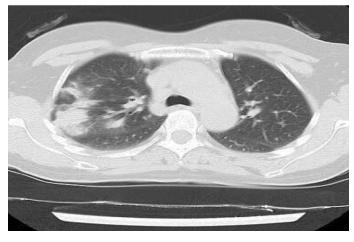

流感,特别是甲流,也会表现为胸膜下为主的磨玻璃,但是出现的几率小于新冠肺炎。

下面的患者,就是甲流病毒性肺炎。